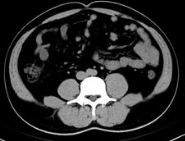

苏州看肝结节专业的医生科普:肝弥漫性结节病变是指在影像学检查结果中显示出肝脏内有多个结节状病变,这种病变可能是良性因素引起也可能是恶性的因素引起的。一般在肝脏内部出现多个大小不一、分布均匀且数量较多小结节,这也是比较典型的病症之一。 肝脏弥漫性结节病变如果与肝脏恶性肿瘤有关... [详情]

苏州看肝脏结节好的医生科普:肝脏上的结节,现在检出率也是越来越高,肝脏多发性结节发生的时候,一般提示肝硬化进展比较严重的阶段,也是肝硬化不典型的增生结节。但是不一定就是到了肝癌的阶段。 对于恶性结节的判断,我们也要知道肝结节边界清晰不一定都是良性的,边界清晰是可以作为判断良... [详情]